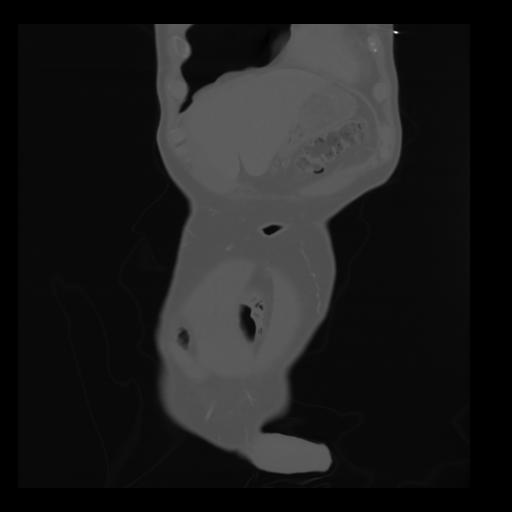

35 CUERPO,CE,Coronal,3.000,CUERPO,Coronal,